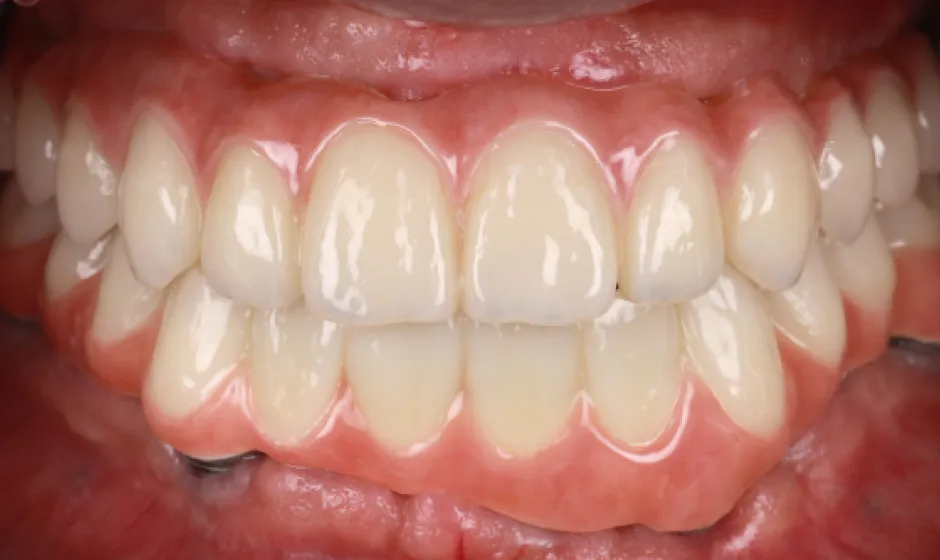

03歯がボロボロの方への

全顎治療むし歯や歯周病が広がり、「どこから治せばいいのか分からない」状態は、痛みだけでなく食事や会話、見た目のストレスにもつながります。大杉歯科医院では、まず精密に検査し、残せる歯・治療が必要な歯を見極めたうえで、治療の優先順位を整理します。仮歯で噛み合わせを整えながら、補綴やインプラントなどの選択肢を組み合わせ、機能と審美の両立を目指します。

いきなり理想を押しつけるのではなく、現実的に続けられる計画で、お口全体を立て直す治療をご提案します。症例1

- 治療名

- 重度虫歯からの全顎インプラント治療

- 患者様

- 70代男性

- 執刀医

- Dr. 大杉

- 治療期間

- 1年6ヶ月

- 治療費

- 上顎:4,620,000円(税込)

下顎:3,630,000円(税込) - リスク

- ラミックのすり減りを防ぐために、ナイトガードを作成しています。毎晩使用することで、セラミックを長持ちさせることができます。

症例2

- 40代男性

- 1年

- 上顎:3,630,000円(税込)

- 術後、硬い物を食べないでください。

インプラントが骨に結合するまで2ヶ月かかります。

この期間中に強い負荷をかけると、結合しないことがあります。